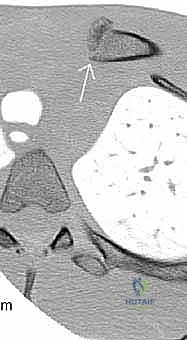

المفصل القصي الترقوي: بوابة خطرة إلى المنصف

يعتبر المفصل القصي الترقوي (Sternoclavicular Joint) - وهو المفصل الذي يربط عظمة الترقوة بعظمة القص في منتصف الصدر - منطقة شديدة الخطورة. وخاصة الجزء الخلفي منه. فمباشرة خلف هذا المفصل تقع هياكل حيوية لا تحتمل أي خطأ: القصبة الهوائية، المريء، والأوعية الدموية الكبيرة جداً في منطقة المنصف (مثل الشريان والوريد العضدي الرأسي، والأوعية تحت الترقوة).

إن خلع المفصل القصي الترقوي الخلفي (انزلاق عظمة الترقوة للداخل نحو الصدر) ليس مجرد إصابة عظمية أو مفصلية عادية؛ بل هو حالة طبية طارئة قد تهدد الحياة وتتطلب اهتماماً وتدخلاً فورياً. قد يؤدي هذا الخلع إلى ضغط مباشر على القصبة الهوائية مسبباً اختناقاً، أو تمزقاً في الأوعية الدموية الكبرى. وغالباً ما يستدعي علاج هذه الحالة تخطيطاً دقيقاً ووجود جراح صدر وأوعية دموية للأطفال على أهبة الاستعداد بجانب جراح العظام.

- الأشعة المقطعية (CT Scan): يطلبها الدكتور هطيف في حالات الكسور المعقدة داخل المفصل، أو عند الاشتباه في خلع المفصل القصي الترقوي، حيث توفر صوراً ثلاثية الأبعاد دقيقة للغاية لتخطيط الجراحة.